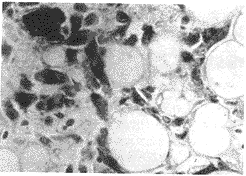

摘要 目的 探讨HMB-45与肾血管平滑肌脂肪瘤的相关性及诊断价值。方法 应用免疫组化技术对43例肾肿瘤进行了HMB-45及多种抗体的检测。结果 肾血管平滑肌脂肪瘤组织中HMB-45有良好表达,而其他肿瘤组织中均无HMB-45表达。结论 HMB-45的表达在肾血管平滑肌脂肪瘤的鉴别诊断中是一个有价值的指标。